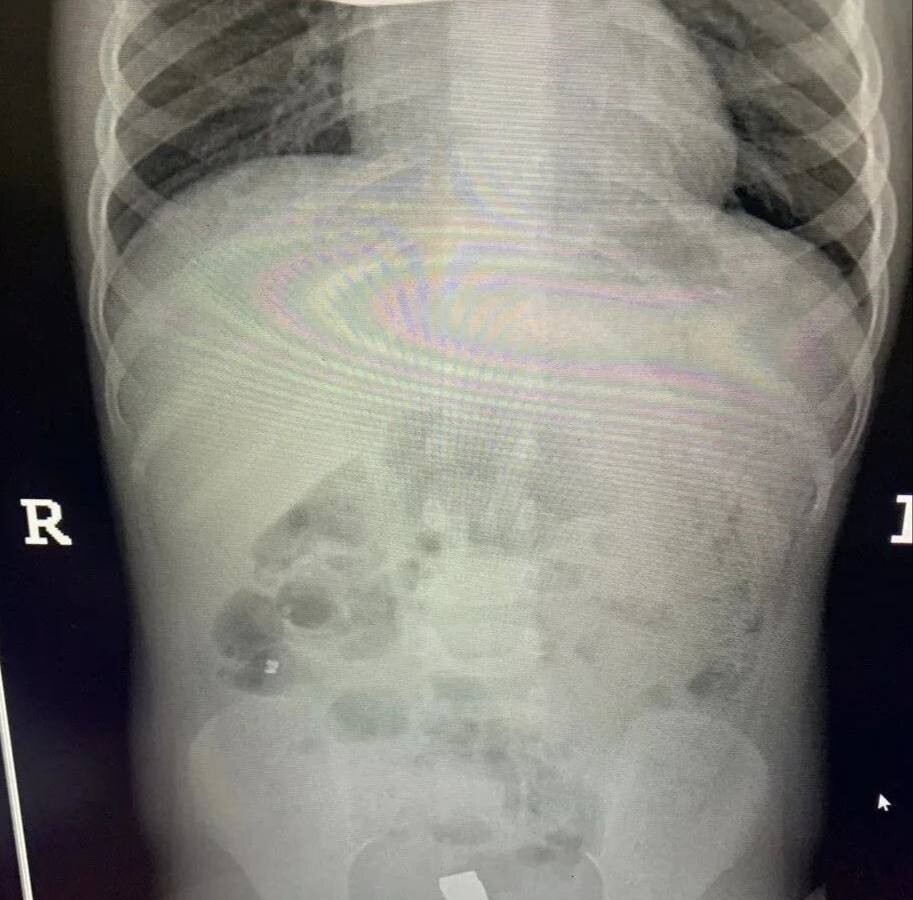

Инцидент произошел в Балашихе — малолетнюю пациентку с жалобами на острую боль в животе доставила в больницу бригада скорой помощи. Обследование показало, что внутри у ребенка большое количество металлических инородных тел. Девочку немедленно отправили на операционный стол.

Врачи приняли решение обойтись без полостного вмешательства. Через крошечные проколы специалисты аккуратно извлекли 20 магнитов из организма ребенка — они успели притянуться друг к другу и прожечь стенку кишки насквозь. Пять штук и вовсе мигрировали в область малого таза.